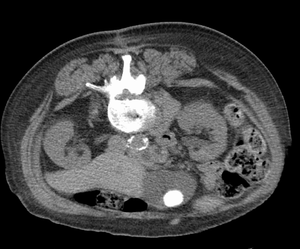

Файл:LargeGstone.png

Крупный желчный камень, видимый на КТ

Самым популярным методом диагностики Желчнокаменной болезни является ультразвуковое исследование. В случае проведения УЗИ квалифицированным специалистом необходимость в дополнительных обследованиях отсутствует. Хотя для диагностики может использоваться также холецистоангиография, ретроградная панкреатохолангиорентгенография. Компьютерная томография и Магнитно-резонансная томография с большей точностью позволяют диагностировать течение болезни.